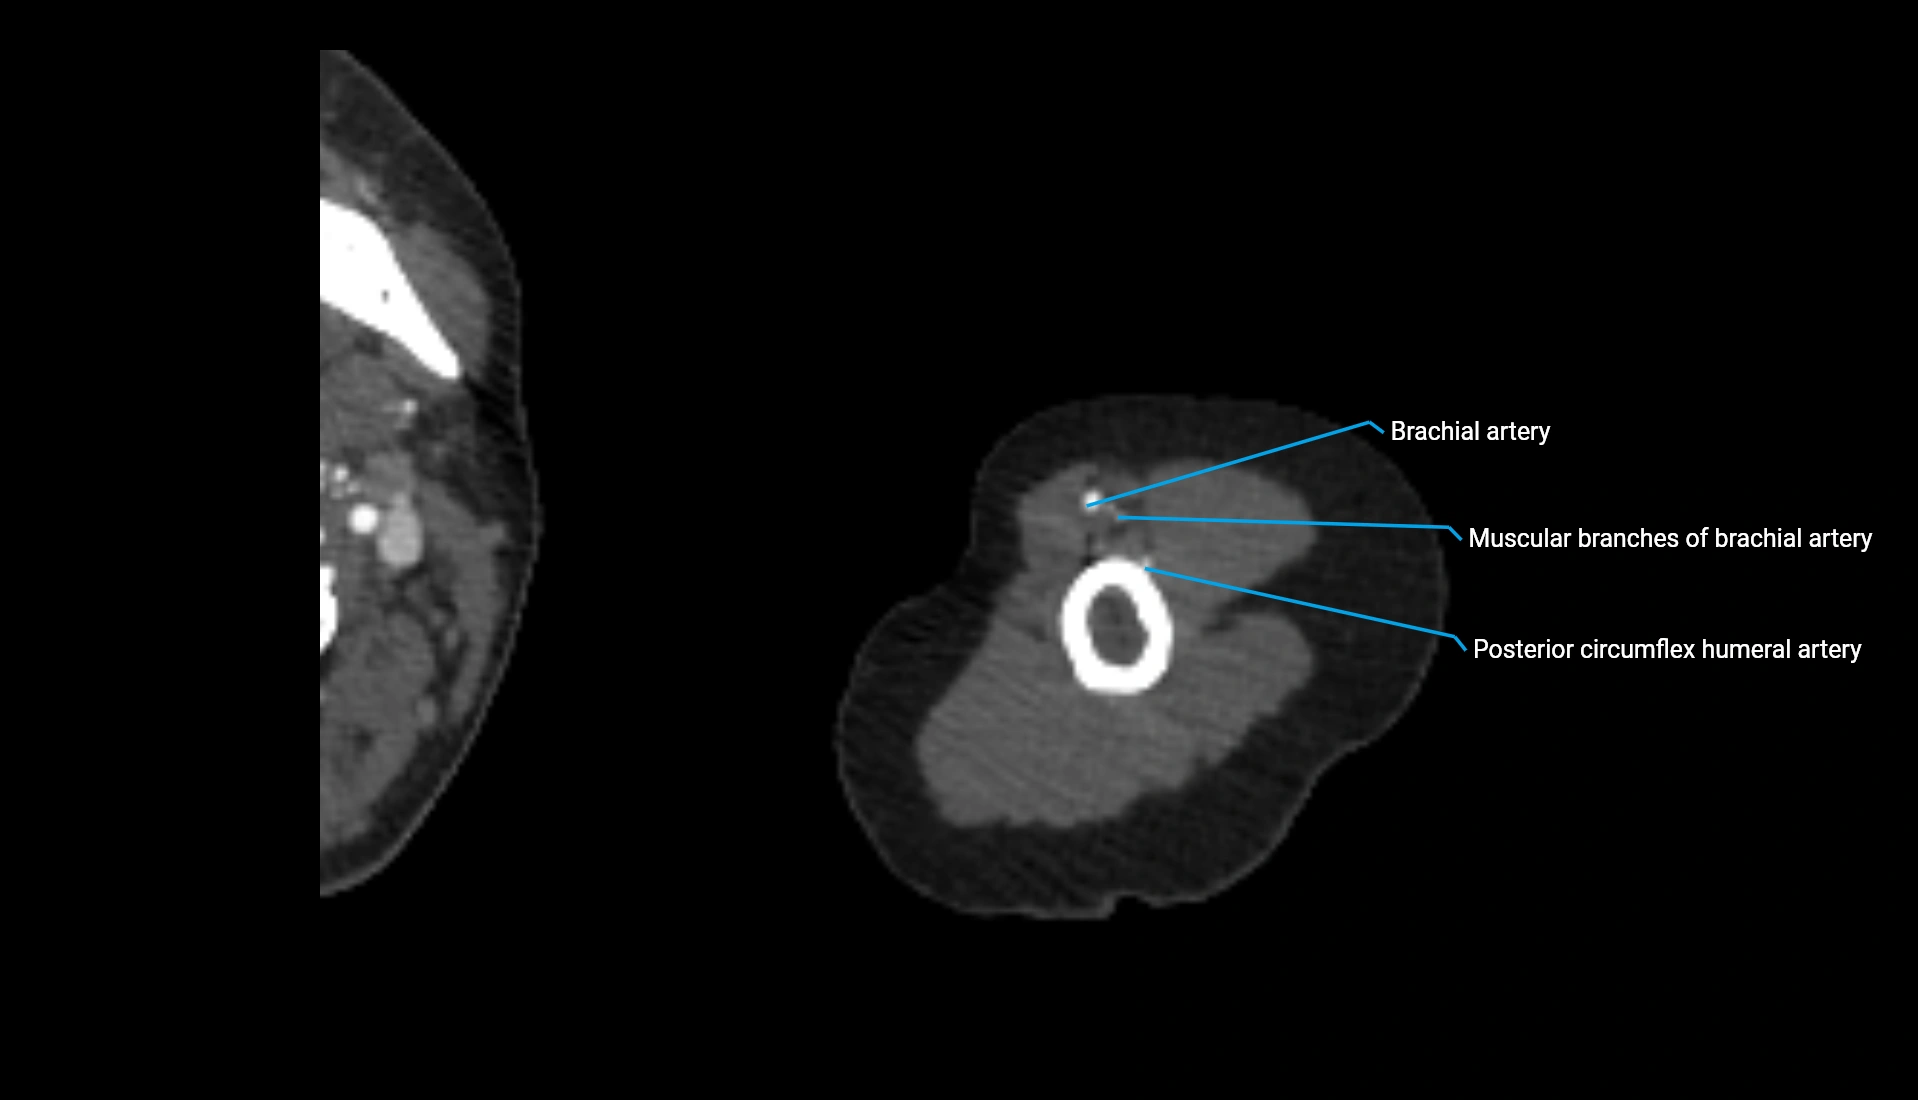

CT Appearance

Non-Contrast CT:

• Cortex: High-density, sharply defined

• Subchondral bone: Dense cancellous matrix

• Articular surface: Smooth concave contour articulating with the capitellum

• Excellent for evaluating bone integrity, alignment, and subtle fractures